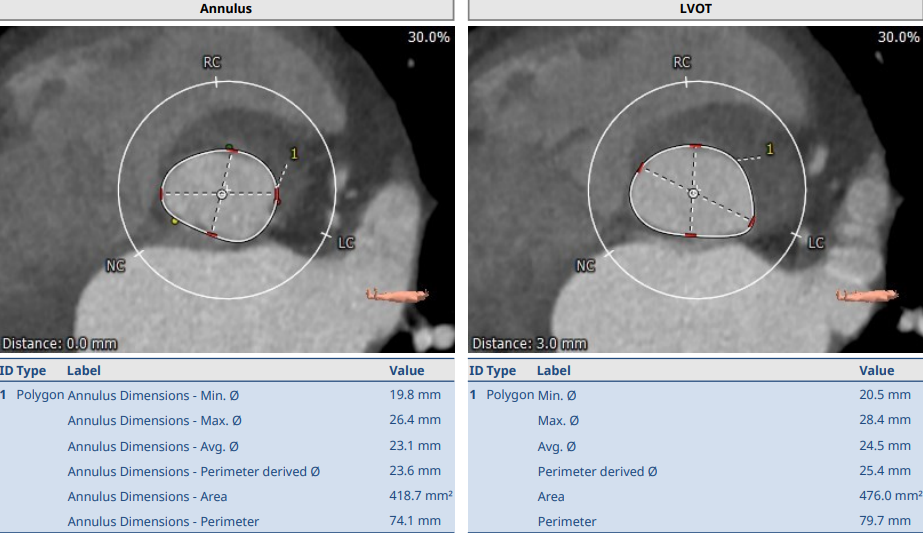

术前CT

中度钙化四叶瓣,瓣环面积:418mm²,流出道面积:476mm²,左冠开口高度:12.2mm,右冠开口高度:9.2mm。